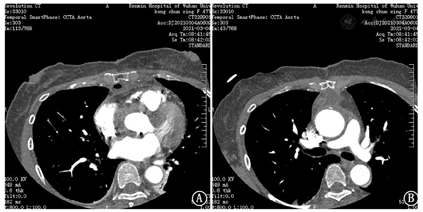

超敏肌钙蛋白I:0.103 ng/mL;胸痛三联CTA示:1.主动脉未见明显狭窄、夹层及动脉瘤征象;2.肺动脉未见明显栓塞;3.右冠状动脉起于左窦,近段纤细;左冠前降支近段非钙化斑块,管腔轻度狭窄(图2)。

本例患者首诊行急诊胸痛三联CTA检查除外了主动脉夹层、肺动脉栓塞,但冠状动脉存在一定异常,结合心电图及血清酶学表现,临床初步诊断考虑为急性冠脉综合征。入院后超声心动图提示主动脉瓣中-重度关闭不全及主动脉窦部夹层,对CTA进行复片提示主动脉根部伪影,仍不支持主动脉夹层诊断,但外科术中证实为主动脉窦部夹层。CTA漏诊主动脉窦部夹层的原因可能是:1、CTA检查易受心脏运动产生的图像伪影影响,且伪影多发生于主动脉近端,本例患者主动脉夹层撕裂内膜局限于主动脉窦部,恰好位于CTA伪影多发部位,造成CTA结果判断偏差;2、尽管胸痛三联CTA是实现胸痛一站式诊断的首选检查,但存在充分显示冠状动脉、肺动脉及主动脉的CTA增强目标各不相同的缺陷[3],理论上如果三个血管都显影意味着与此同时四个心腔里都会被造影剂填充,浓度过高的造影剂就会导致硬化线束伪影的产生,从而影响特别是右冠和肺动脉起始部位的观察,本例患者CTA见升主动脉根部见线样低密度影,延伸至腔外,故放射科医师根据经验判断为主动脉根部伪影,导致主动脉窦部夹层漏诊。